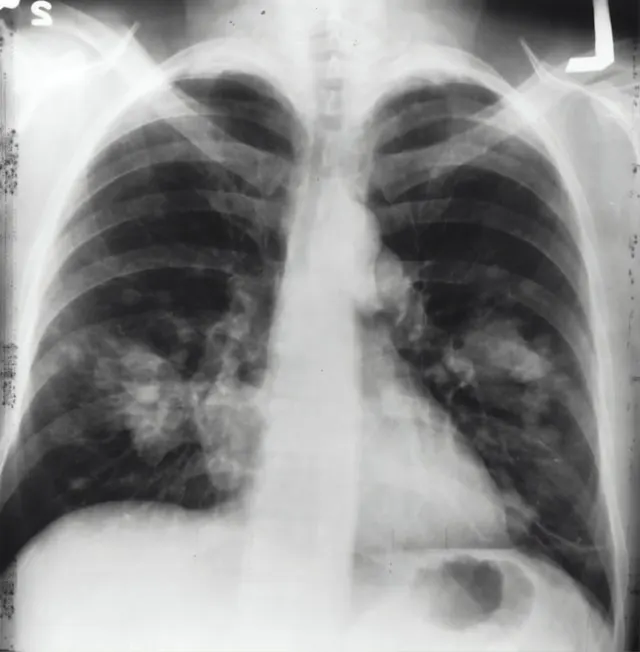

갈비뼈 금 갔을 때 증상이 해당하는 분들은 최대한 빠르게 병원에 가셔야 합니다. 응급실이나 정형외과를 방문하시면 되는데요. 엑스레이와 정밀진단을 통해 다양한 치료법이 제시될 수 있습니다.

가슴 부위의 통증으로 숨을 쉬기가 힘들어집니다. 숨을 쉬기 위해 가슴 부위에 움직임이 발생하면 통증이나 불편함이 생기게 됩니다. 기침이나 가래에 피가 섞여 나오는 경우도 있습니다.